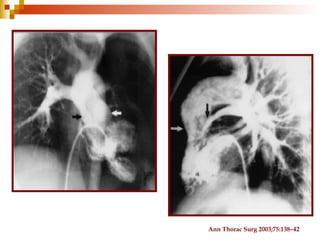

Cateterismo cardiaco

Ann Thorac Surg 2003;75:586–7

Ann Thorac Surg 2003;75:138–42